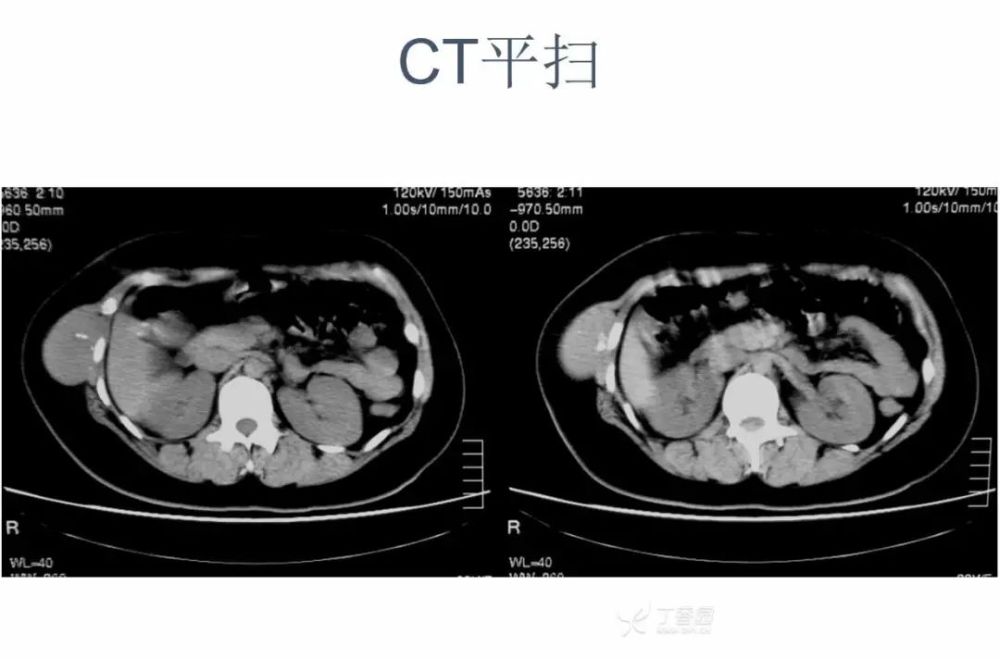

女,22 岁。右下侧胸壁疼痛、不适 10 年,近 3 年发现右侧腋中线近肋弓处肿块。体检:局部皮肤无红肿,肿块质中等偏硬,活动度欠佳,压痛( + ),无血管杂音。超声描述「低回声包块」。化验室指标无异常。